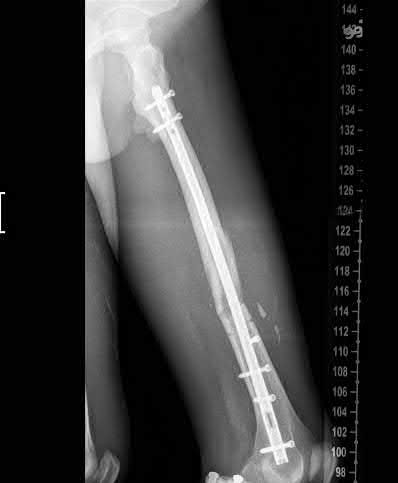

Question 17

A 32-year-old male sustains a closed tibia fracture and develops intense leg pain out of proportion to the injury. You suspect acute compartment syndrome.

Which of the following pressure parameters is considered the most reliable threshold indication for performing a four-compartment fasciotomy?